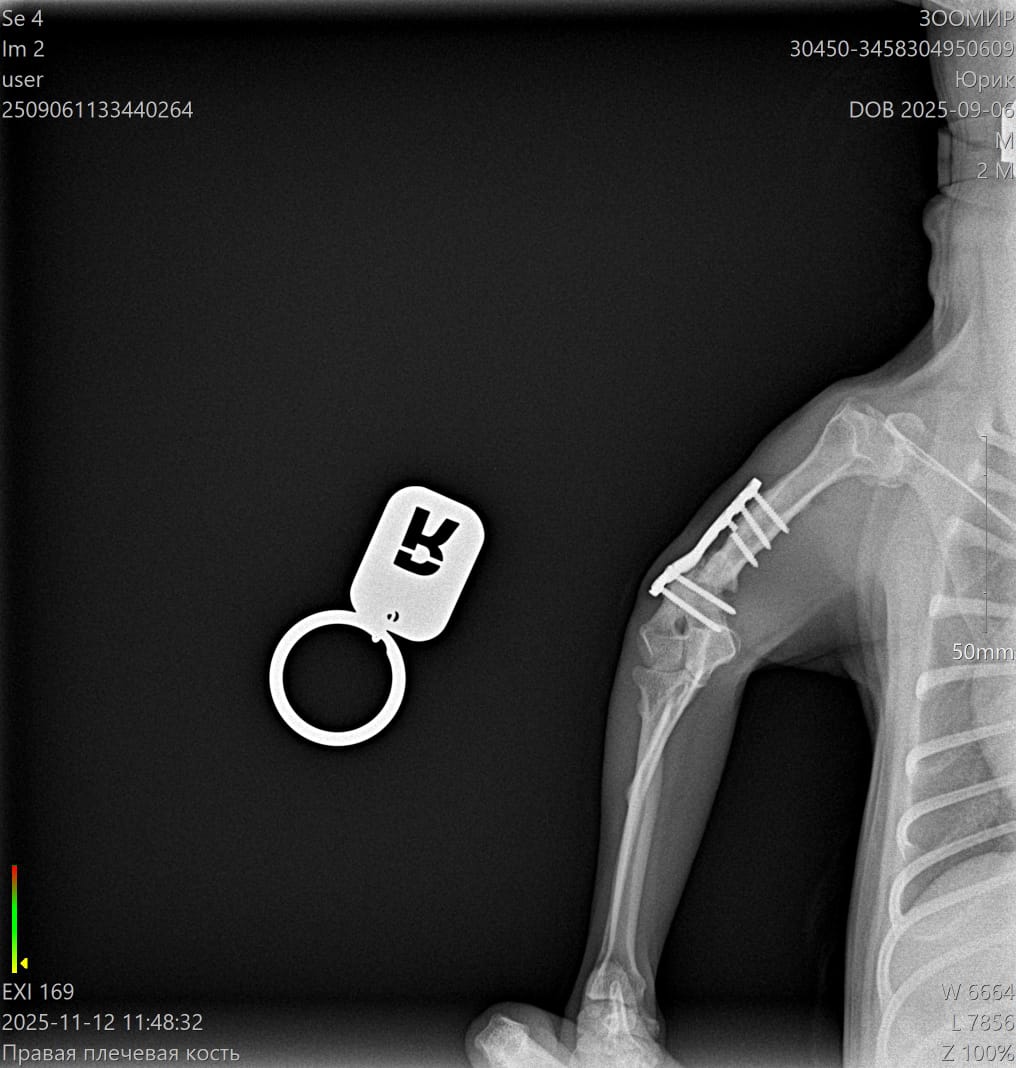

Юрик съездил сегодня на контрольный рентген.

Больная лапа вернула свой нормальный размер и окрепла.

Ходит и тянет на всех четырех. Быстро летает по пересеченной местности - бережет. Видимо не удобно, что покороче.

Мозоль ОБРАЗОВАЛАСЬ. По центру она еще не очень плотная, но кость срослась.

Как Ольга паразита не оберегала, но на рентгене оказалась чуть погнутая пластина и один сломанный винт.

Снимать ничего не будем из конструкции, если не начнет отторгаться или двигаться.

2 рентгена и осмотр АН обошлись в 2600₽ ( это стоимось 2 снимков).

Юрик. Взгляд изнутри